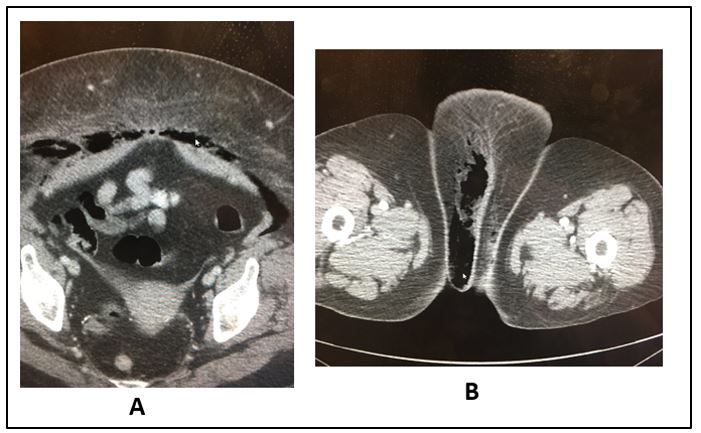

Figure 2. CT scan pelvis (A); lower cut same scan (B)

Answers What does the CT scan show: The CT shows an atrophic uterus with gas (black) tracking just behind the abdominal wall extending over the rectus sheath (Figure 1; Figure 2A). A lower cut (Figure 2B) shows gas tracking into the labia majora on the right (click on Figures to enlarge).